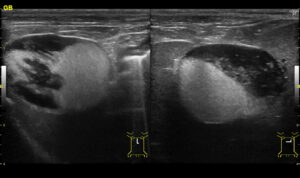

血液検査・レントゲン検査・エコー検査によって診断を行います。

中でもエコー検査は重要で、胆嚢内部の状況を確認するために必須の検査になります。

血液検査にて肝酵素の上昇や、エコーにおいて胆泥貯留が認められ胆嚢粘液嚢腫・胆嚢炎の疑いがあったため手術を行いました。